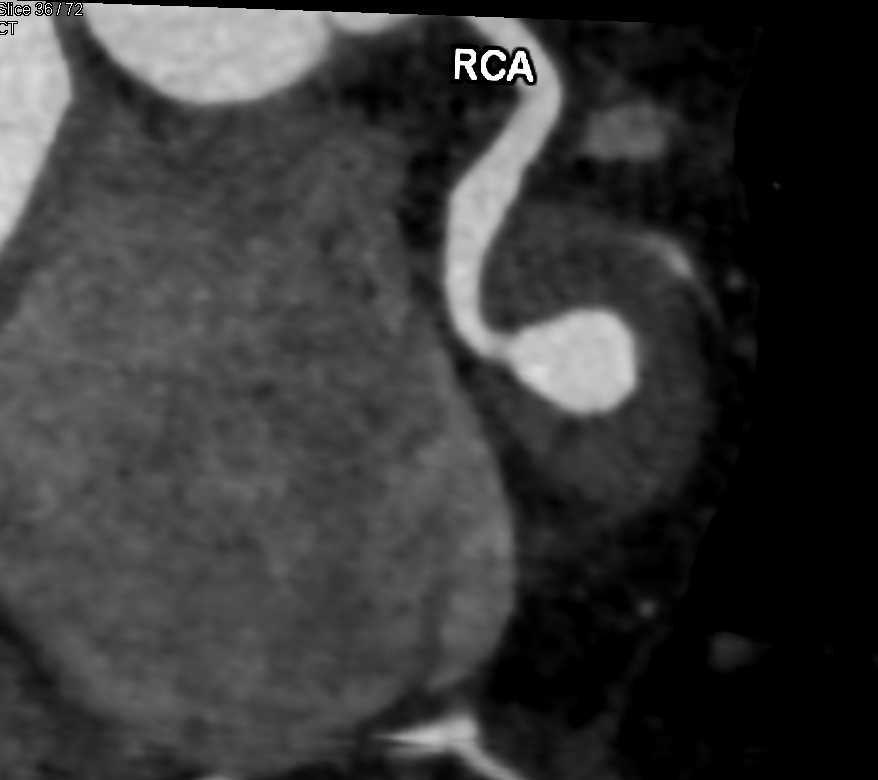

CCTA: Right Coronary Artery Aneurysm